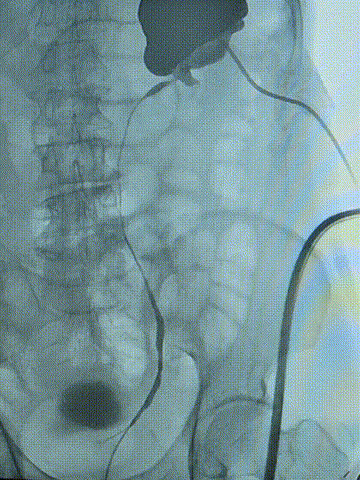

术前造影